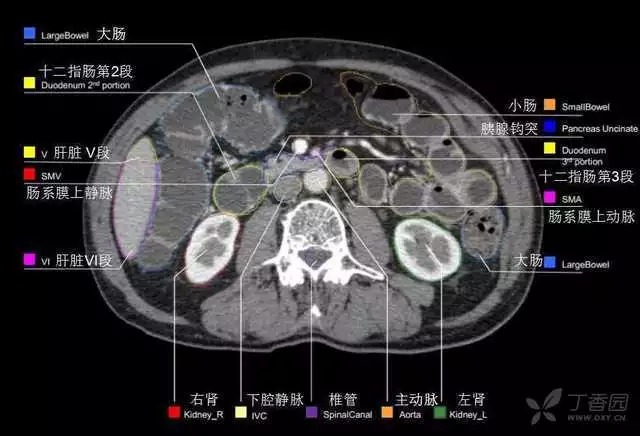

腹部肝脏高清CT断层的图谱

全腹部高清CT图谱,淋巴结彩色图谱,血管解剖图谱大汇总!